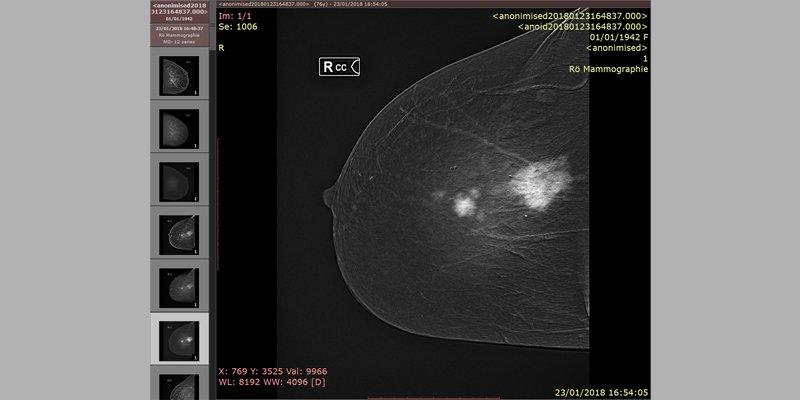

Kontrastförstärkt mammografi, bild från Fuji